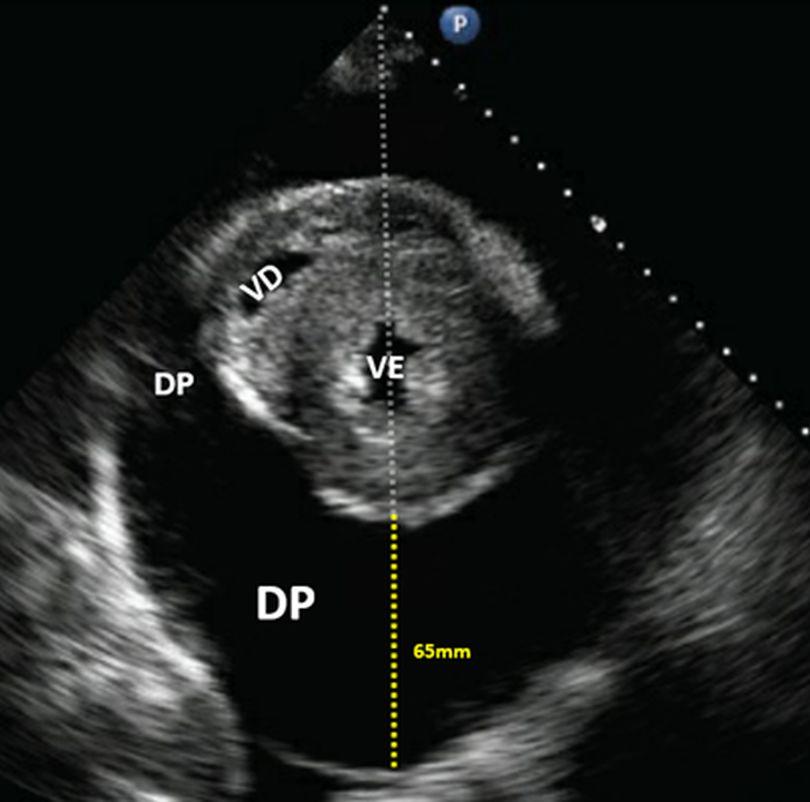

Em ecocardiografia existem inúmeros critérios que muitas vezes exigem experiência prática para avaliação de líquido no pericárdio. Mas quando um iniciante na técnica, e mais particularmente um não eco…